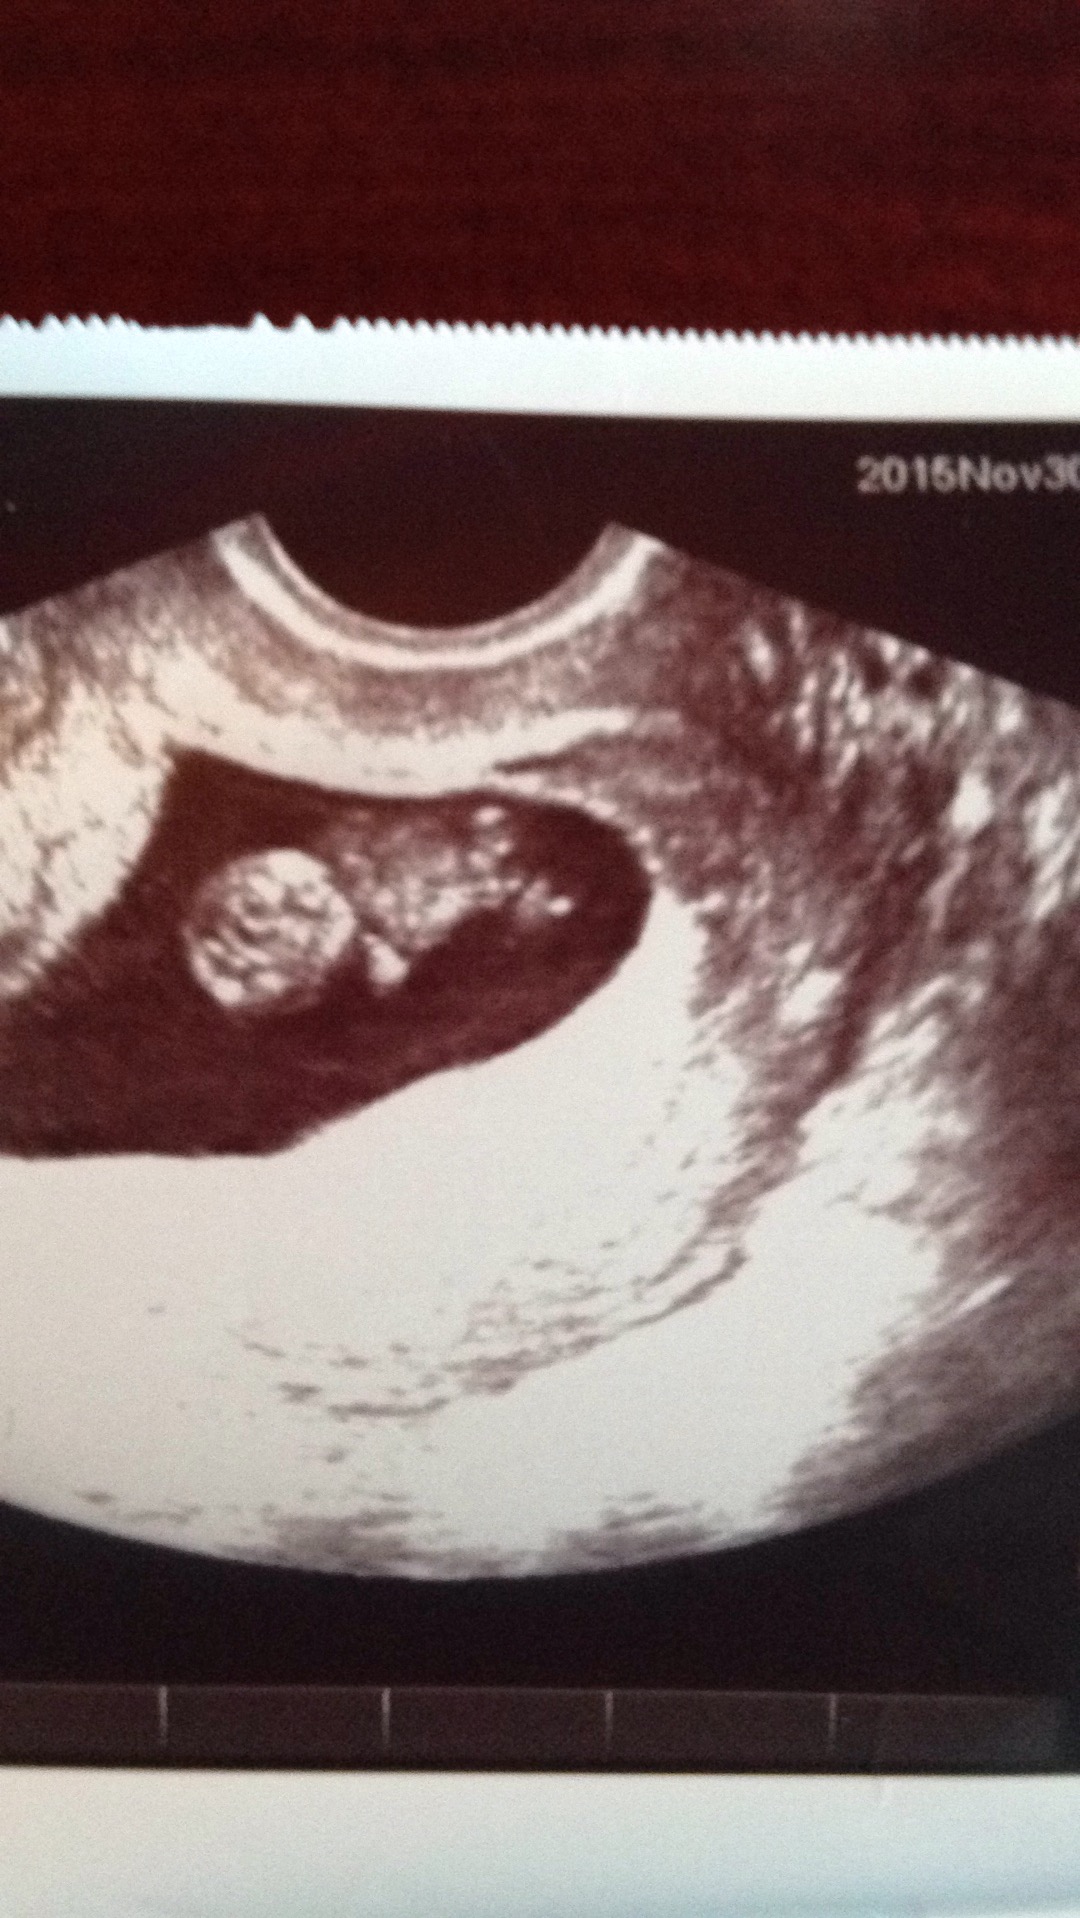

Baby has grown so much!!! It's no longer a little peanut like when we saw it for the first time at 6w3d. Today at 10w3d he/she was waving and kicking the feet around, heartbeat of 160 something. My heart is bursting with love for this precious little life.

Here's our nugget at 10w!!! So happy to see he/she moving around and the little heartbeat at 160BPM (Sorry had an error with the above post not sure how to delete it)